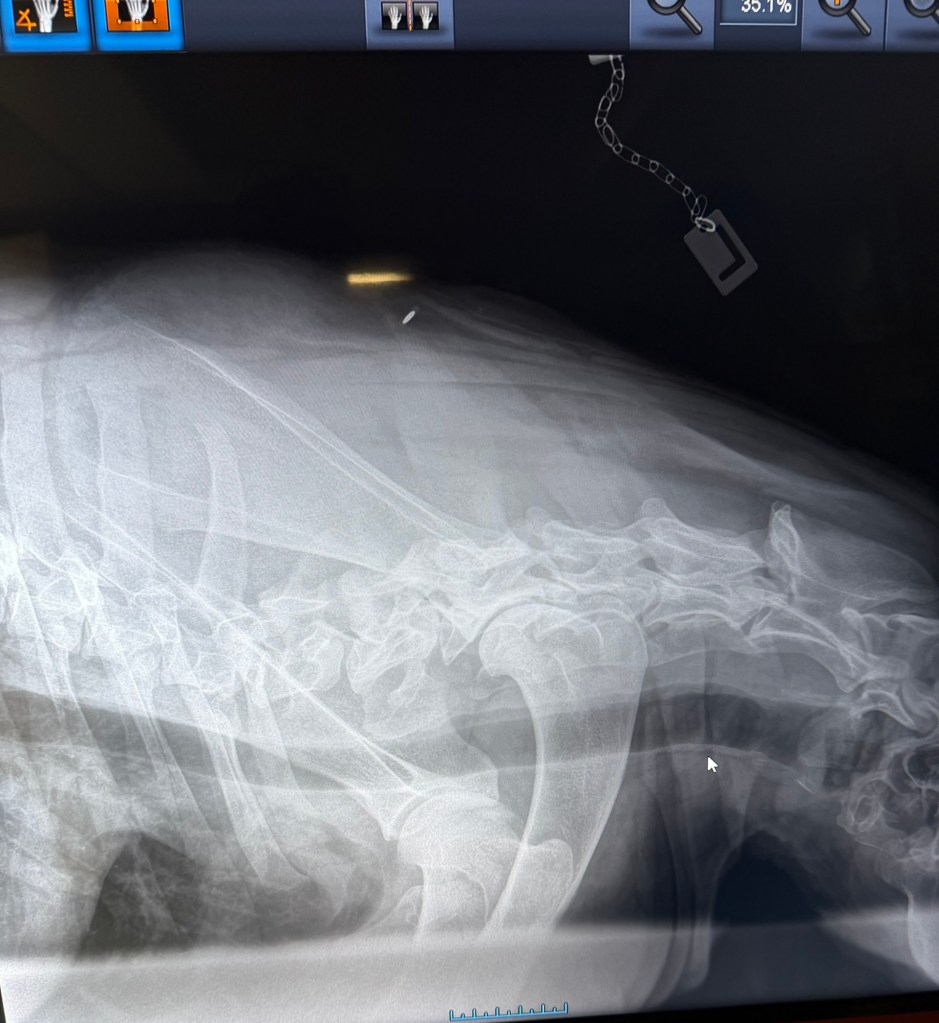

Geri var på ny røntgen nå i november 2025, i en alder av 3år og 8måneder. Dette for å være ansvarlig og forsikre meg om at det ikke blir avl på foreldredyr som har feil utvikling og avdekke svakheter hvis de eksisterer.

Det viste seg å være meget positive resultater (legger ved noen av bildene). Ingen forkalkninger og fremdeles fine albuer, ingen forandring fra 18 måneder HD/AD røntgen til nesten 4års alder. Hun har også en meget fin rygg, og spesielt god og robust lenderygg (bak) som er et fokus område for schæferhunden.